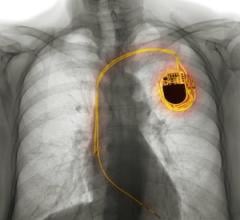

Feb. 9, 2026 — Argá Medtech has announced positive clinical results from the BURST-AF (NCT05572047) first-in-human trial ...

Feb. 6, 2026 — Abbott has announced new clinical data from two late-breaking presentations at AF Symposium in Boston ...

Jan. 28, 2026 — Corify Care has announced a major development in cardiac electrophysiology with the publication of its ...